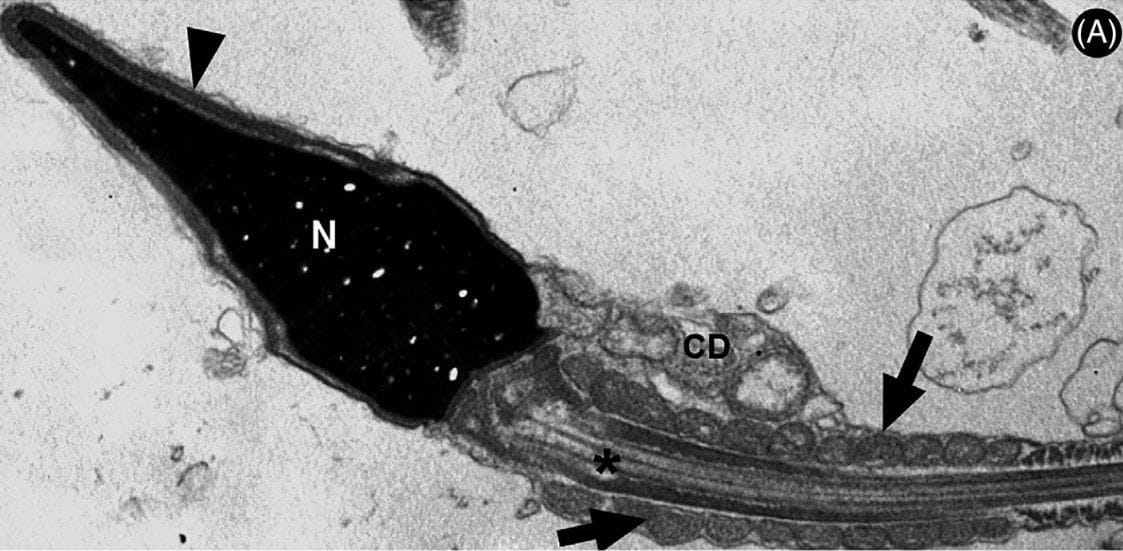

Mais de quatro anos após o início da pandemia de COVID-19, já se sabe que o novo coronavírus é capaz de invadir e destruir uma série de células e tecidos humanos. Os testículos funcionam como “porta de entrada” para o vírus, que tem sido observado com maior agressividade no trato genital masculino. O estudo atual, financiado pela FAPESP, utilizou tecnologias de PCR em tempo real e microscopia eletrônica de transmissão para analisar o material genético do vírus em espermatozoides de homens convalescentes de COVID-19.

Foram examinadas amostras de sêmen de 13 pacientes infectados, revelando a presença do SARS-CoV-2 nos espermatozoides. A descoberta de que os espermatozoides produzem armadilhas extracelulares baseadas em DNA nuclear para neutralizar o vírus representa uma quebra de paradigma na ciência.